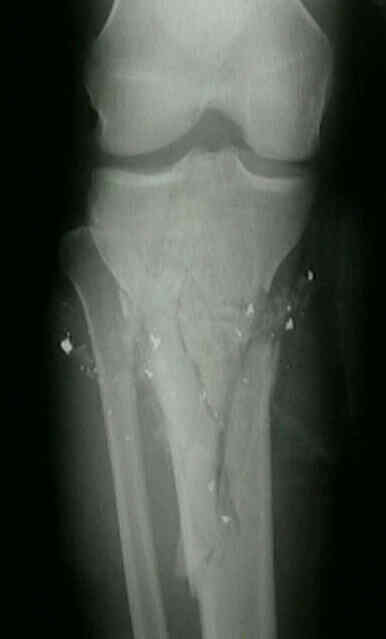

amf1.jpg (67096 bytes)

Herida por arma de fuego: disparo con arma de caza en pierna